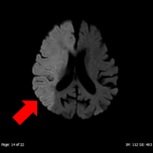

- 頭部MRI

| 頭部領域では、CT では分かりにくい脳梗塞や微小脳出血、脳腫瘍などの精査を目的とした撮影を行います。本検査では造影剤を用いることなく血管の描出をすることができ、血管狭窄、塞栓症などの診断にも有用です。病態によってはより詳しく調べるために造影剤を使用することもあります。 | ||

| DWI画像 | FLAIR画像 | MIP画像(血流途絶) |

| 心原性急性期脳梗塞 | ||